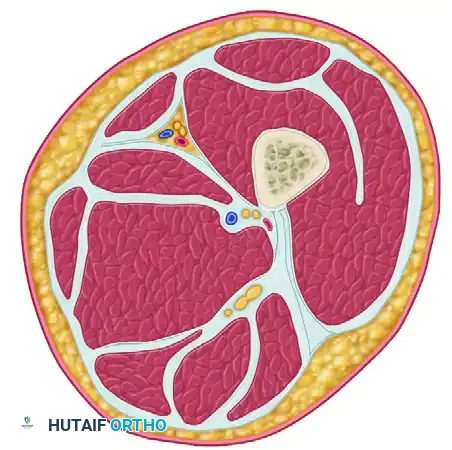

FASCIOTOMY FOR ACUTE COMPARTMENT SYNDROME OF THE LEG

The lower leg is the most common anatomical site for acute compartment syndrome. It consists of four rigid compartments: Anterior, Lateral, Superficial Posterior, and Deep Posterior.

Surgical Technique: Four-Compartment Decompression (Davey, Rorabeck, and Fowler)

This technique utilizes a single, highly expansile lateral incision to access all four compartments of the lower leg. While a two-incision technique (anterolateral and posteromedial) is also widely accepted, the single lateral approach described by Davey et al. is highly effective when performed with precise anatomical knowledge.

Undermine the skin anteriorly to expose the fascia overlying the anterior and lateral compartments. Identify the anterior intermuscular septum dividing these two compartments. Perform a longitudinal fasciotomy of the anterior compartment, taking care to protect the superficial peroneal nerve, which exits the lateral compartment to become subcutaneous in the distal third of the leg. Subsequently, perform a longitudinal fasciotomy of the lateral compartment.

Step 3: Superficial Posterior Compartment Release

Undermine the skin posteriorly from the primary incision to expose the fascia of the superficial posterior compartment (containing the gastrocnemius and soleus muscles). Perform a longitudinal fasciotomy to release this compartment.

Step 4: Deep Posterior Compartment Release

This is the most technically demanding step. Develop the interval between the superficial posterior compartment and the lateral compartment. Identify the fibula. The flexor hallucis longus (FHL) muscle must be dissected subperiosteally off the posterior aspect of the fibula and retracted posteromedially. Once retracted, identify the deep fascial attachment of the tibialis posterior muscle to the fibula. Incise this fascia longitudinally to completely decompress the deep posterior compartment.